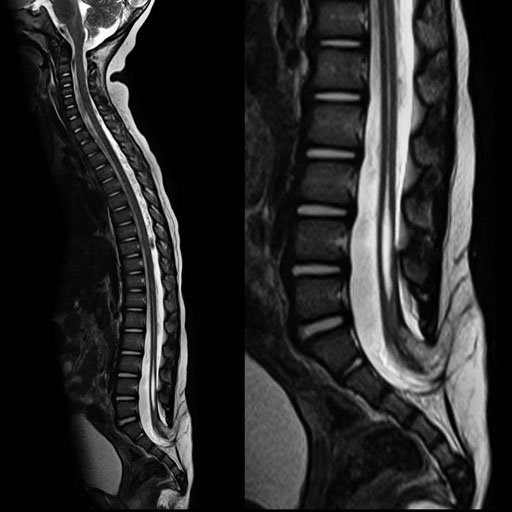

| Syringomyelia and tethered cord. age 22 months.

syngo GRAPPAx2(45 sec. 418 matrix.3mm) |